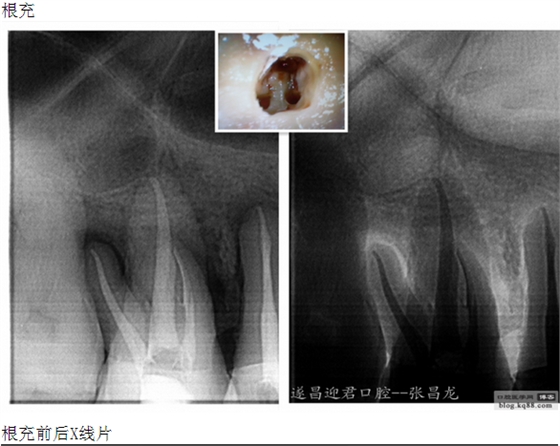

每個牙科醫(yī)生都不愿碰到器械分離,但常在河邊走,哪有不濕鞋的,我想大部分醫(yī)生根管治療中都發(fā)生過器械分離吧。在此就不在累贅那些造成根管器械分離的原因,醫(yī)生們也都知道那些。遇到器械分離莫慌,我們還是有挽救的余地。由于醫(yī)生的技術(shù)原因,設(shè)備原因,不是每個斷針都能取出來的。與對一部分斷針我們可以嘗試建立旁路通道,斷針與根管壁之間的間隙慢慢通入到工作長度,然后常規(guī)根管治療。

下面是我最近的一個患者,患者14,15,16均因楔狀缺損導(dǎo)致牙髓壞死,根管治療期間,16的近中頰根發(fā)生了斷針。